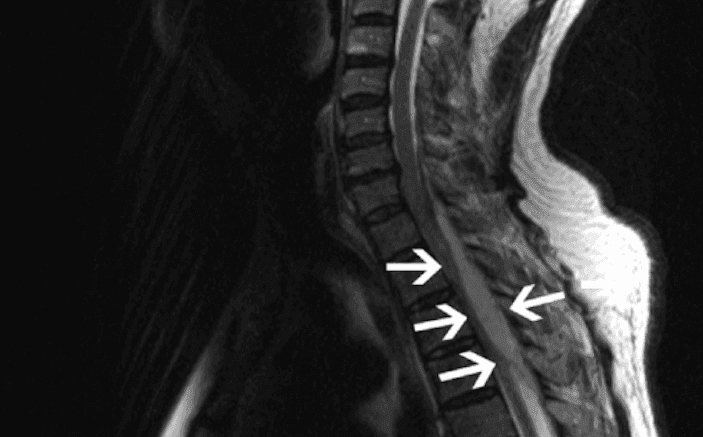

الورم الحبلي: الأسباب والأعراض والتشخيص والعلاج

خراج فوق الجافية: الأسباب والأعراض والتشخيص والعلاج